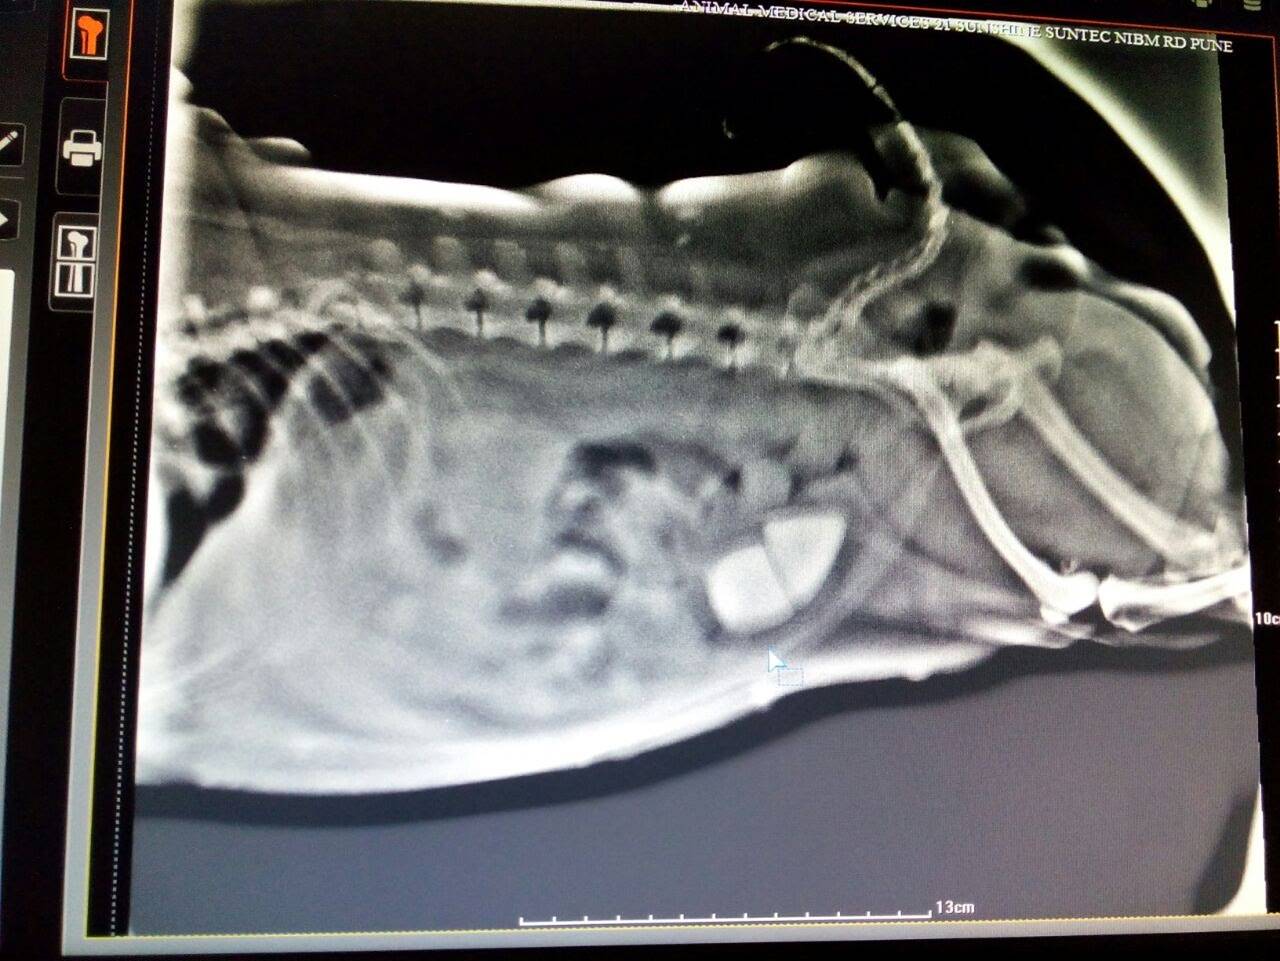

Radiopaque Stones Dog . Urinary stones (urolithiasis) are a common condition responsible for lower urinary tract disease in dogs and cats. Cystine (hexagonal) crystals are pathognomonic for cystinuria, but crystalluria is absent in many dogs with cystinuria. They are correct that urate and cystine are the least radiopaque of the common stones in dogs and cats. However, there is significant overlap between types of stones. Radiographs may help provide some insight into stone type; One of the best methods to make a diagnosis of uroliths is radiography. The formation of bladder stones ( calculi ) is associated with precipitation. Stones vary from radiographically invisible to mildly radiopaque. These smooth to slightly rough, relatively large radiopaque stones are often round or angular and usually associated with a staphylococcus or. 5 ultrasonography can identify radiolucent stones such as urate, xanthine, and small cystine stones. Blood in the urine (called hematuria) and. The most common signs of bladder stones in dogs are: Straining to urinate (called dysuria).

Radiographs may help provide some insight into stone type; 5 ultrasonography can identify radiolucent stones such as urate, xanthine, and small cystine stones. The most common signs of bladder stones in dogs are: Straining to urinate (called dysuria). Blood in the urine (called hematuria) and. These smooth to slightly rough, relatively large radiopaque stones are often round or angular and usually associated with a staphylococcus or. Cystine (hexagonal) crystals are pathognomonic for cystinuria, but crystalluria is absent in many dogs with cystinuria. However, there is significant overlap between types of stones. They are correct that urate and cystine are the least radiopaque of the common stones in dogs and cats. One of the best methods to make a diagnosis of uroliths is radiography.